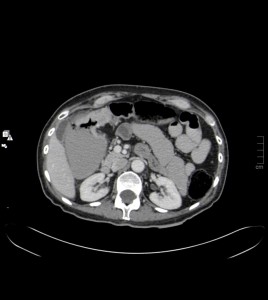

La TC se ha convertido en la técnica de imagen más importante en la evaluación de pacientes con dolor abdominal en el servicio de urgencias.

Una característica única de la TC es que permite evaluar la pared del colon así como los tejidos pericólicos y estructuras adyacentes, siendo una técnica muy sensible para demostrar patología colónica tanto intra como extramural.

Nos ayuda gracias al estudio de diversos parámetros, pudiendo realizar un diagnóstico diferencial preciso que no se puede alcanzar con otras técnicas. Estos parámetros incluyen: localización y extensión de la afectación, la apariencia del engrosamiento parietal y la presencia de anomalías en estructuras vecinas y a distancia.